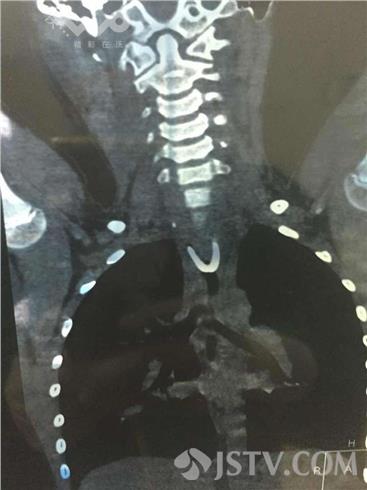

在儿童医院办公室,荔枝新闻通讯员见到了这块儿被取出来的u型猪骨,至少2cm长,两端十分尖锐。该院消化内科内镜室副主任医师练敏向笔者介绍,CT片显示u型猪骨头很大,两个尖端牢牢卡在食管上端的软组织里面,骨头非常粗,非常硬。“虽然以往取出的异物不计其数,但这么大的异物、卡得这么死的还是头一次。而且这块猪骨靠近主动脉和心脏,距离主动脉血管仅2公分,食管壁已有两个可疑创孔,如果刺破附近的心脏,后果不堪设想。”练敏这样说道。